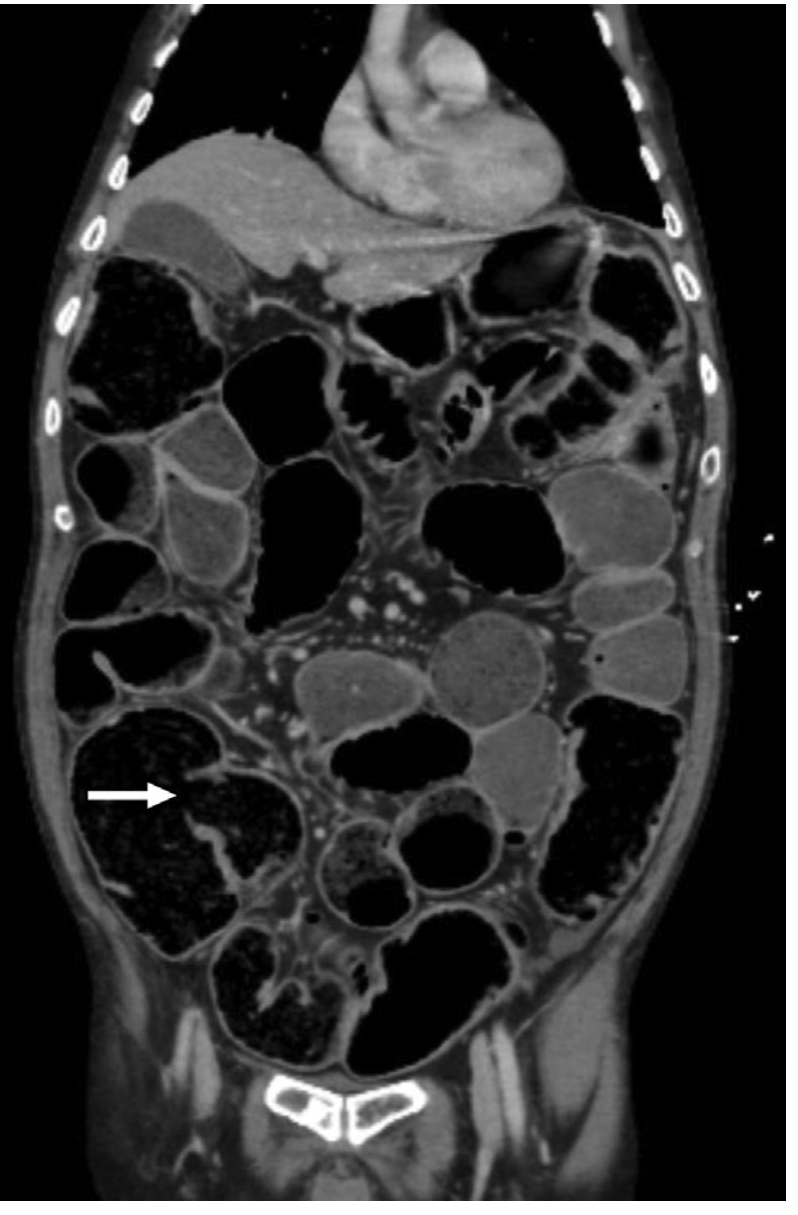

CT coronal image of complete LBO due to sigmoid adenocarcinoma, showing massive small bowel dilation from incompetent ileocecal valve (arrow)

Coronal CT scan showing complete large bowel obstruction with massively dilated bowel loops throughout and transition point in the sigmoid (arrow)